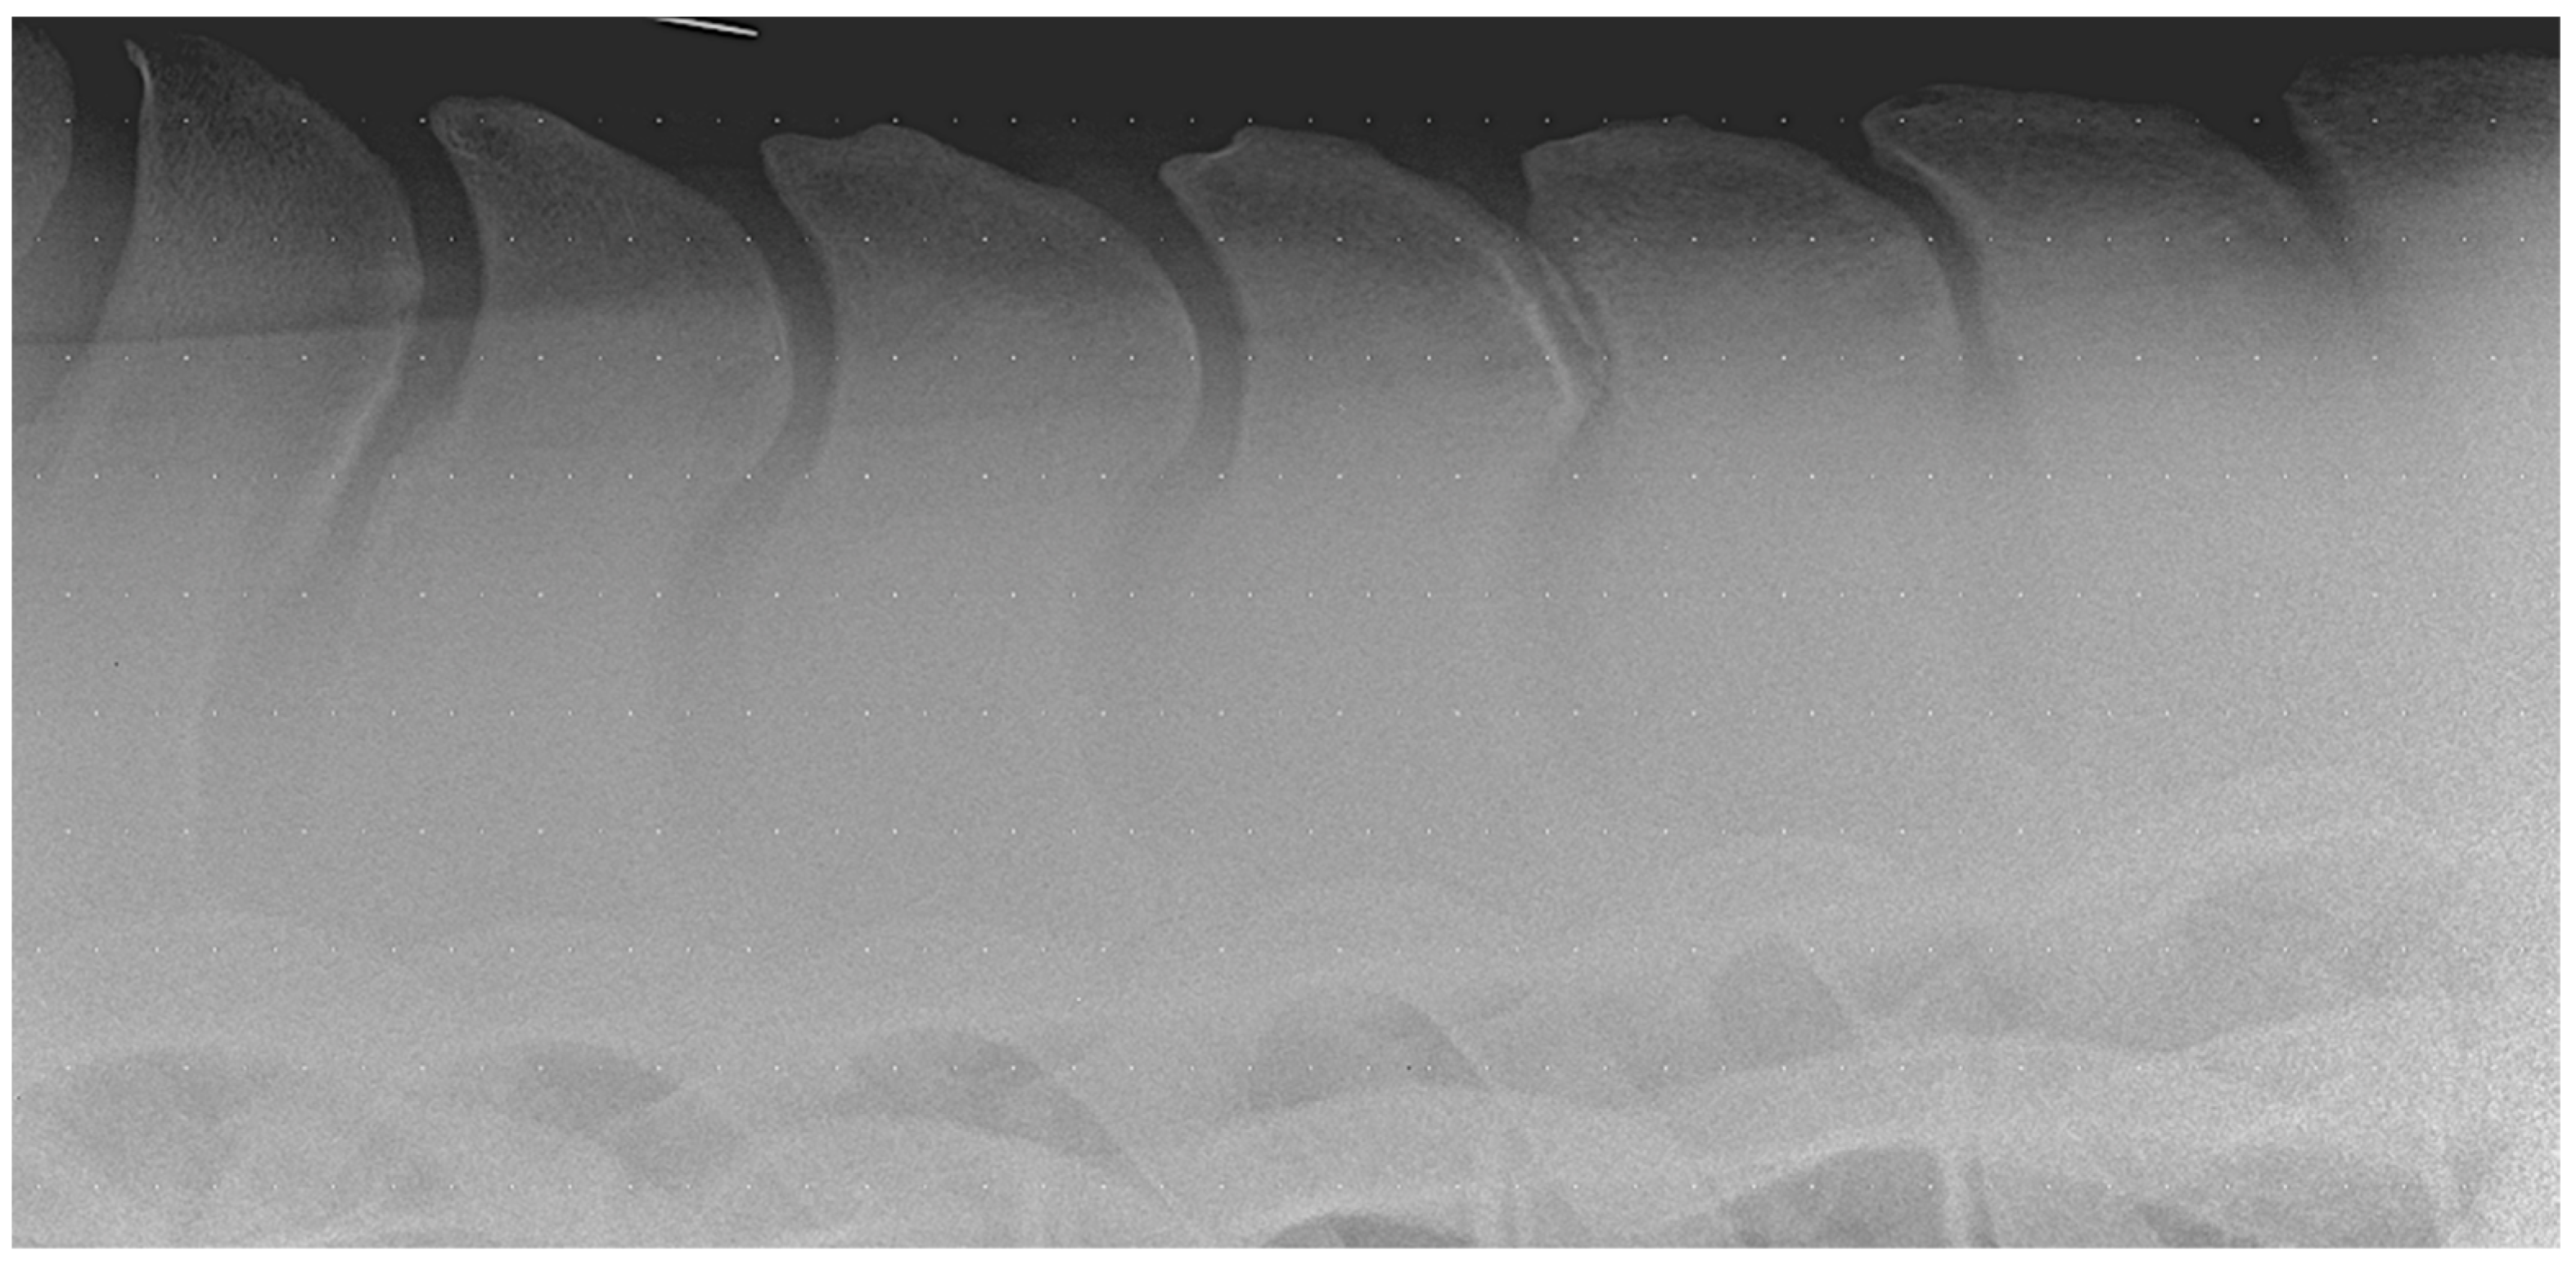

5.2. Diagnostic Imaging Findings